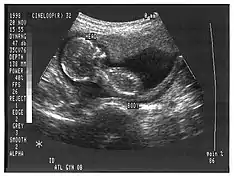

A ultrassonografia pode contribuir como auxílio no diagnóstico médico e veterinário, sendo sua aplicação mais ampla atualmente em seres humanos. Esta técnica tem sido muito utilizada em obstetrícia, sobretudo na avaliação de aspectos morfofuncionais. Permite ainda a orientação de processos invasivos mesmo antes do nascimento.

A ultrassonografia é um dos métodos de diagnóstico por imagem mais versáteis e ubíquos, de aplicação relativamente simples. Por não utilizar radiação ionizante, como na radiografia e na tomografia computadorizada, é um método relativamente inócuo, pouco dispendioso e ideal para avaliar a evolução fetal. Nas últimas duas décadas do século XX, o desenvolvimento tecnológico transformou esse método em um instrumento poderoso de investigação médica dirigida, exigindo treinamento constante e uma conduta participativa do examinador.[2]